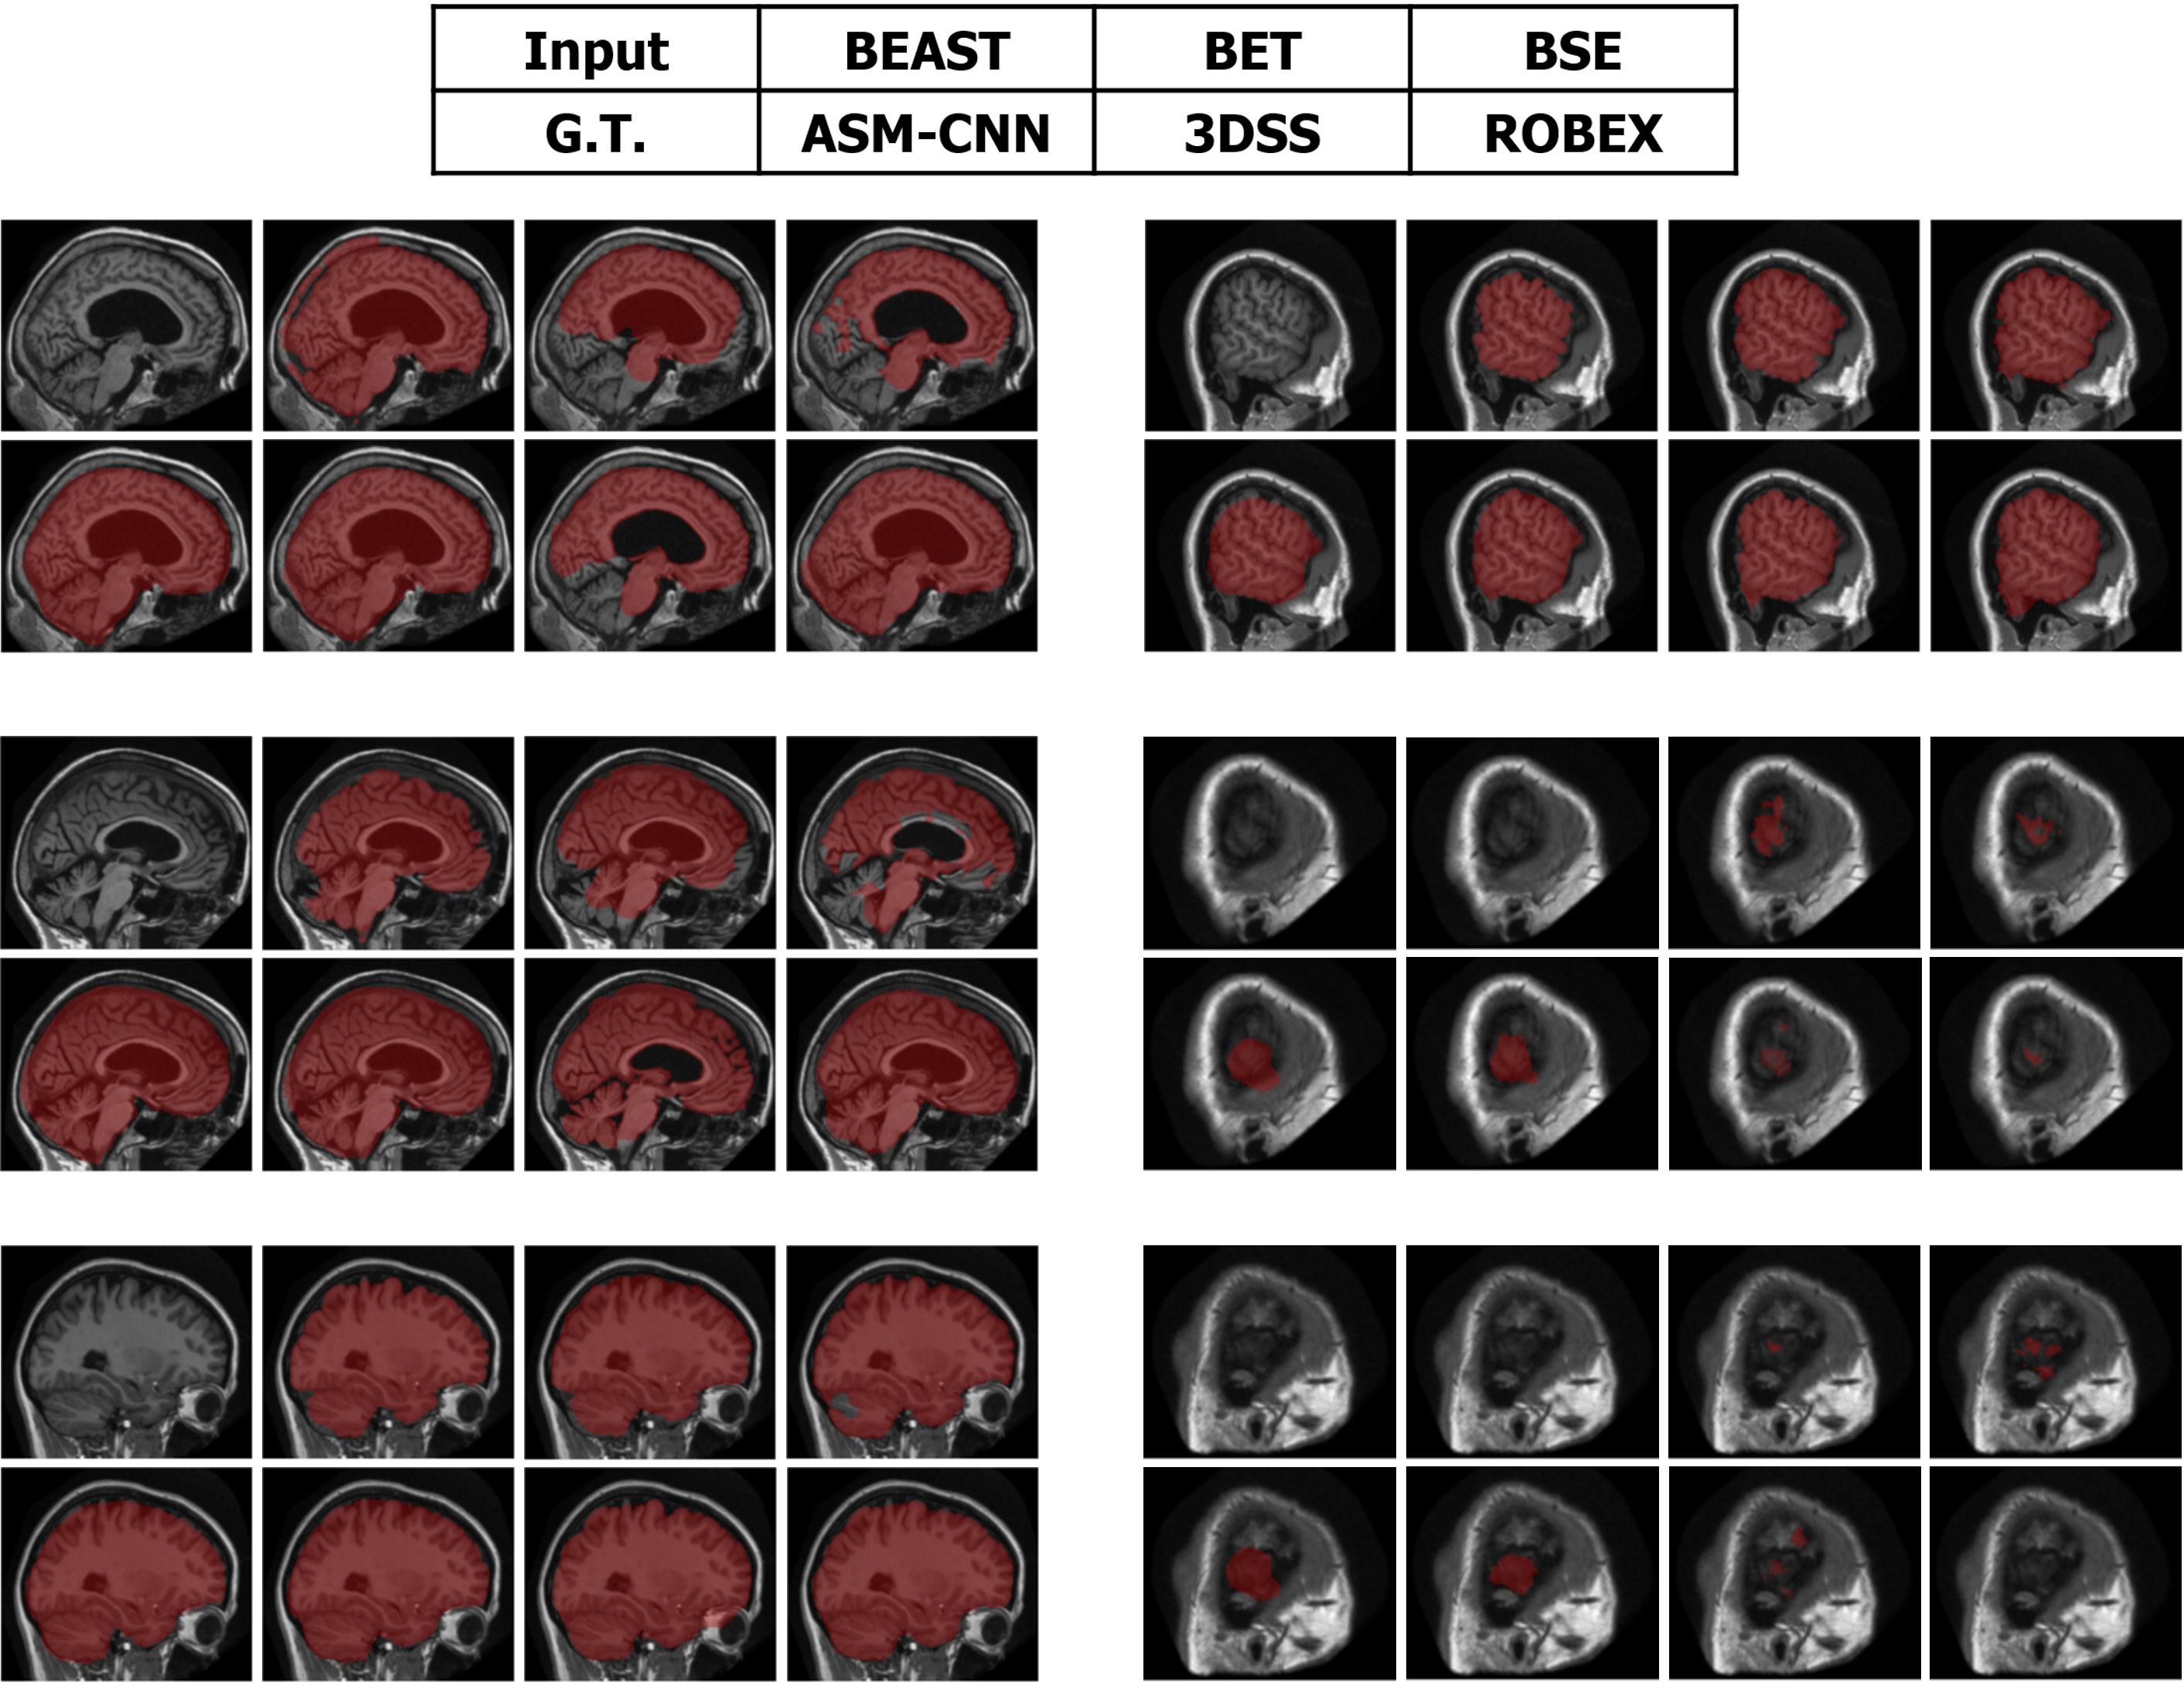

Segmentation results of ASMCNN and seven other methods in the sagittal plane for the three datasets are illustrated in Figures 11, 12 and 13 respectively. Each figure includes six typical testing scans from all three groups (two scans for each group). Although ASMCNN works with the sagittal plane, it also produces correct segmentation in two other planes. Figure 14 shows the comparison between our approach and other methods on each dataset for these two planes.

Refer to caption

Figure 12: The comparison between ASMCNN with other methods on OASIS dataset.

Figure 13: The comparison between ASMCNN with other methods on LPBA dataset.

ASMCNN can provide extremely accurate segmentation in these three datasets. We achieve the same results as ROBEX with smooth boundaries and keep both gray and dura matter inside extracted brains for most cases, which are usually left out by ROBEX. Although there are minor leakages into the skull by ASMCNN, its occurrence is less than both ROBEX and BEAST, as it only generates a smaller number of over-segmentation results. The critical impact of the method is that it can precisely work for small-size brains in Group I as well, meanwhile other techniques usually fail. As shown in Figures 11 - 13, our results are mostly similar to the ground-truth images especially for tiny-size brains (Figure 11). The method does not avoid a few false negatives and false positives in this group on account of the complexity of the brain structure. Nevertheless, ASMCNN can mostly obtain a better performance than others with higher accuracy.

Figure 14: Resulting images on transverse and coronal plane for IBSR, LPBA, OASIS dataset.